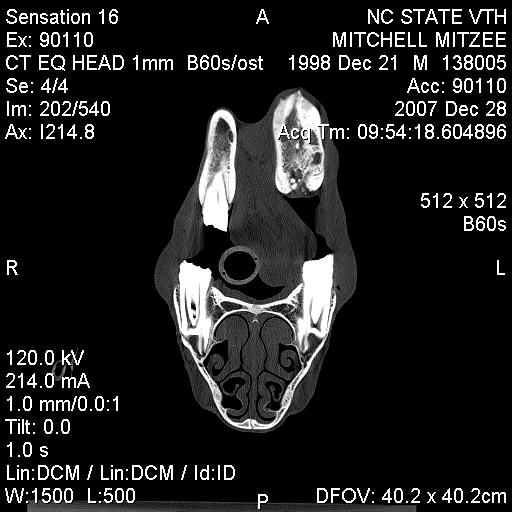

Posted on Sunday, Jun 24, 2007 - 3:39 pm: Greetings Everyone,I have finally received some of Mitzee's xrays, though it appears that I'm missing several... hmmm... Anyway, I thought I would give everyone an update. After two weeks of inpatient care (IV antibiotics, anti-inflamatory agents, a few different wound site I&Ds, several xrays and another fistulogram, etc...), she was discharged on 6/7/7. The final fistulogram showed NO evidence that the draining sinus tract communicated with the adjacent tooth root (4th premolar), but, rather, seemed to travel to the empty alveolar socket of her previous surgical site (the removed 3rd premolar). I had decided I did not want to attempt to manage her on my own, so I arranged to board her and Rorie at a facility owned by an equine vet, kind of like a lay up hospital situation... She's been getting daily assessment and care of her wound, the barn has a great fly control system and, so far, she usually goes out at night and stays in during the hot day. Plus, when she and Rorie are out, they're with other mare/foal pairs and that's a nice bonus for Rorie. Mitzee's eating well, her weight is good, and her activity is normal. And, though tissue healing is occurring, significant swelling of her left submandibular area persists and there are two remaining tracts that drain purulent material, though it is less than previously observed. I have decided to see how things go for awhile and "embrace" this conservative approach... clearly, the surgeon was not interested in pursuing more surgery at the time of her discharge, though when I corresponded with him recently (and showed the same pictures I am posting below) he suggested we get a CT scan. Of course, a CT scan appears to require general anesthesia and I would have to take her to a larger referral, probably academic, center. Based on where I am in VA, the closest facilities are NC State in Raleigh, NC, Marion duPont Scott in Leesburg, VA, or VA Tech in Blacksburg, VA... I do still worry that there's something "left behind" in the wound, perhaps a necrotic bone fragment???, that is continuing to feed this low level infection... At this point in time, she is almost 6 weeks postop from her initial surgery to remove premolar #3... Rorie was 8 weeks old last Tuesday... What does everyone think???? Thanks! Martha

Posted on Tuesday, Jan 1, 2008 - 11:08 pm: Hey Everyone,Sorry for the delay in posting the images... Mitzee was discharged on Sunday (POD 2) and I DrOve down to NC, picked her up, and travelled back to VA in the worst pouring down rain (not complaining, we still do have DrOught conditions a bit...) Anyway, I was on call the next day (New Years eve) and had a killer night, so I am still kinda brain dead today... I've managed to crash my laptop several times with the disc I was given at NC State... just wondering if it has anything to do with my new laptop OS, Vista, but now, finally, I've managed to load some of the study pictures onto my old laptop (hopefully the keyboard won't quit like it did this summer). The plain xray is not great... possibly me altering it in the download process??? Anyway, it is a lateral so you see both sides of the jaw and you have to focus on the near structures (the left side), not the far ones (the right side); basically, it shows distortion of the the left lower premolar #2, which has occurred following removal of #3 last May, and compensatory changes in the left upper arcade (see the big ramp/points above). The few CT views I've uploaded show extensive bony proliferation and periosteal reaction of the left hemimandible, an absent left lower 3rd premolar tooth, as well as some radioopaque densities below this area, presumed to be ?tooth fragments or cement debris following the previous surgery; there is one particular linear density located in the center of this area that was felt to represent a possible "sequestrum" and was removed... also, you can see a radiolucent tract that exits the lower portion of the left hemimandible below the empty alveolar area of the absent 3rd premolar. A lytic lesion is seen associated with the lateral aspect of left lower 4th premolar near the gingival margin and another draining tract travels between this front/rostral portion of the left lower 4th premolar tooth and the lateral aspect of the mandible; my discharge papers state that the CT findings "are consistent with peridontal abscessation and a draining tract", however the surgeon believes the root and pulp of the left lower 4th premolar tooth are still healthy, so we may have a ?50/50 chance of saving that tooth. I have also attached a few other pictures of Mitzee undergoing her CT scan under general anesthesia, her recovery from GA, and a view of the her face following the surgery where the diseased areas were debrided. Her discharge papers note the final diagnosis as "chronic osteomyelitis of the left mandible and peridontal disease adjacent to left mandibular premolar tooth #4". I'll keep everyone posted on her recovery. Thanks!!! Martha

Posted on Monday, Jan 7, 2008 - 4:56 pm: O.K., I am going to try and load the CT images again... please refer to my descriptions of them above. Also, the surgeon from NC State called me today and reported the results of the cultures taken during surgery; Mitzee has grown two types of anaerobic, gram negative rod bacteria, a Prevotella "species" and Fusobacterium nucleatum. He said that he had not had a Prevotella isolated from equines in the past, but that the Fusobacterium is a common oral bacteria in a number of species.... Now, the plan had been for Mitzee to receive two weeks of postop antibiotics, trimethoprim/sulfamethoxazole (Bactrim DS) and when I brought her home on POD#2, I was able to give her the PM dose by syringing paste directly into her mouth (she did protest a little); for the next 24 hours, I was on call and during my absence the barn staff failed miserably in getting any drug into her! I certainly didn't want any of the barn staff to sustain injuries, nor did I want Mitzee to be hurt (apparently, she got into her rearing mode...), so I spoke with the surgeon then and he said I could forego her oral antibiotics (afterall, the surgical debridement was the "definitive" therapy!). Today, he mentioned that metronidazole (Flagyl) was the typical antibiotic for anaerobes, but that horses tolerate it even less than the Bactrim she had been on... so, since he felt good about the debridement, we are not treating her with antibiotics. The plan is to (as long as she looks good "clinically") take her back to Raleigh in about 4 weeks so he can examine her oropharynx and HOPEFULLY see that her orocutaneous fistula is HEALED and that the left lower premolar #4 is still O.K.!!! I'll keep everyone posted!Martha P.S. Keep in mind, when looking at the scans below, you are looking at a "cross-section" or axial image of the head, UPSIDE down... remember that she was laying on her backside to undergo the scan... also, the right side of the image is Mitzee's left side... notice the dramatic difference between the two sides, i.e., each hemimandible...